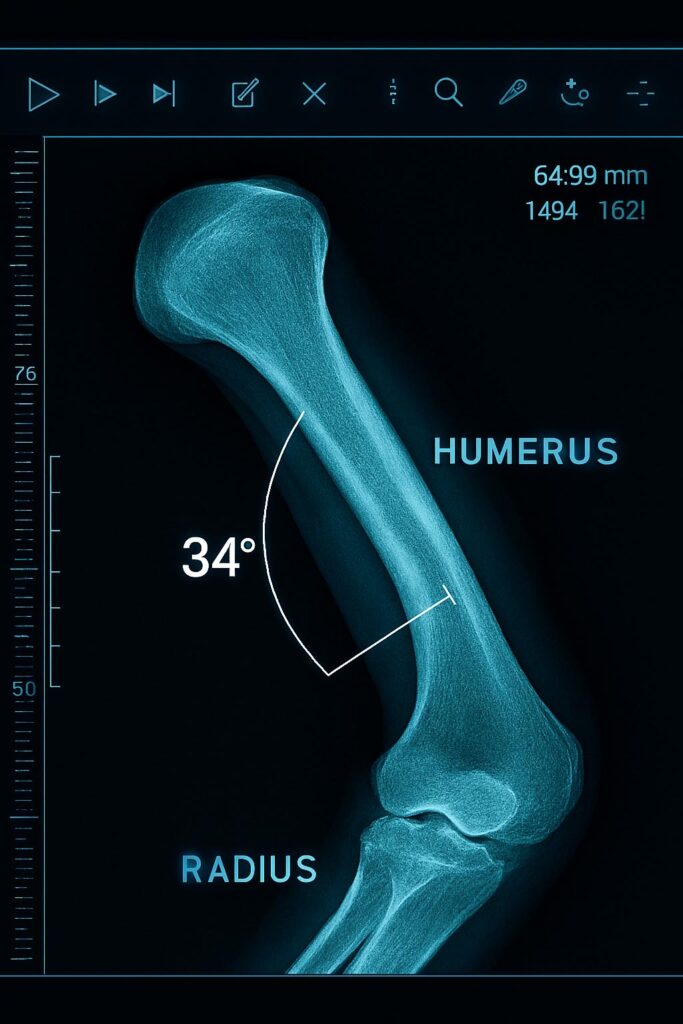

Se realizó una primera consulta por video conferencia y le solicité que necesitaba tener dos TAC, uno de cada brazo; material que me enviaron inmediatamente de forma electrónica.

Los TAC se trasladaron al laboratorio 3D, donde con aparatos e instrumental sofisticado, junto a ingenieros muy preparados (pueden reconstruir el esqueleto de una persona), imprimimos el húmero derecho, dañado, y también el sano, permitiéndonos una comparación perfecta y estudiar el tipo de cirugía que debíamos practicar.

Destrozar no sería la palabra adecuada. Es términos médicos es una osteotomía: cortar el hueso, fracturándolo de nuevo, no hay más remedio. Se trata de un corte limpio, que se hace en el quirófano con una sierra de precisión.

Fue una operación minuciosa, delicada. Pegar el hueso de nuevo, reconstruirlo, no es tan problemático, pero el señor Márquez añadía un problema. Su húmero tenía una rotación de 34 grados, que era, en el fondo, lo que le impedía ejercer su profesión, competir como él quiere. Encontrar el punto correcto de rotación no fue sencillo. Pero la preparación previa en el laboratorio 3D, con simulación y guías de corte precisas, permitió ejecutar la cirugía con seguridad.